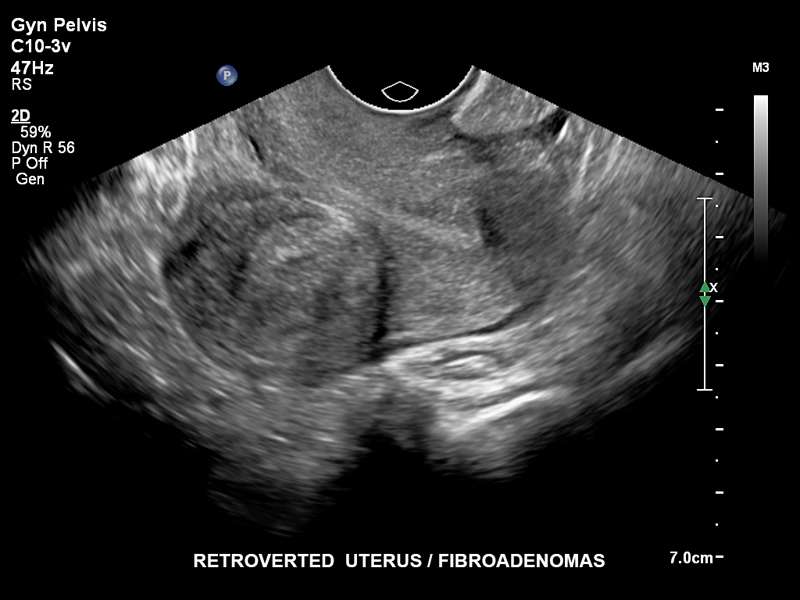

Ретровертированная матка, C10-3v